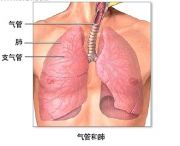

| 2021年7月26日 (一) 20:01 | 慢性支气管炎.jpg (文件) |  |

47 KB | 77921020 | Uploaded with SimpleBatchUpload | 3 |